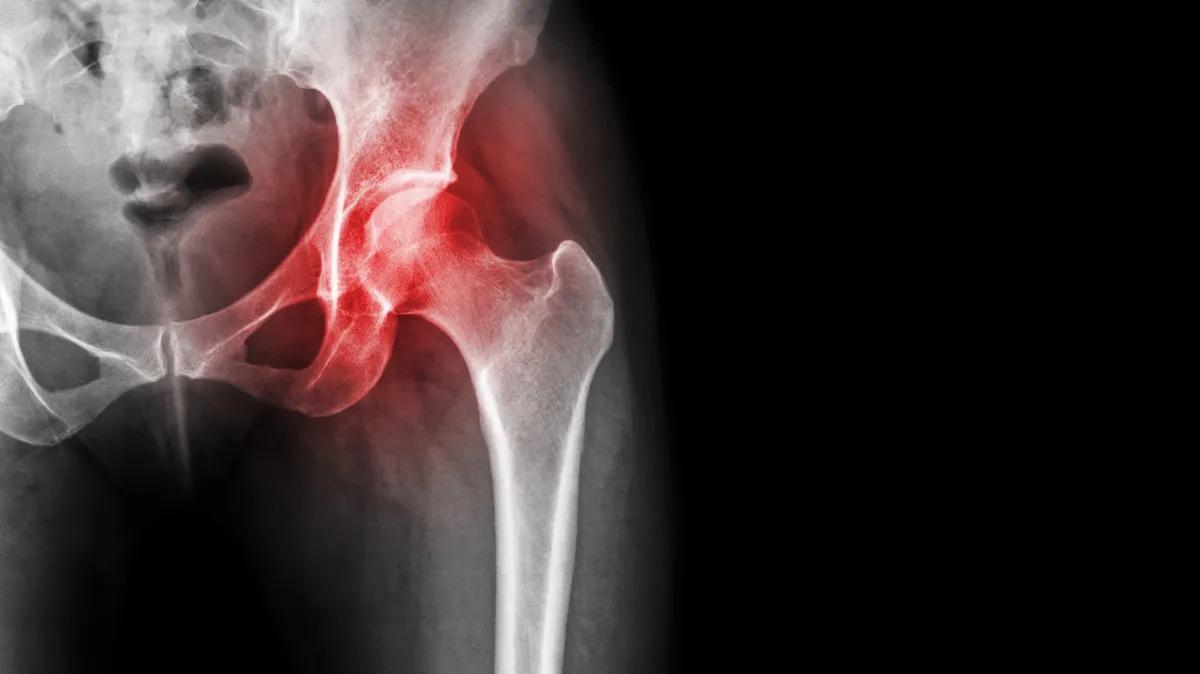

股骨头坏死是骨科常见疾病,发病的主要原因是股骨头供血不足,导致股骨头出现骨质疏松、病变,最终塌陷、坏死。

股骨头坏死,早期的疼痛主要为钝痛、针刺样疼痛以及酸痛,发生部位主要是在下腰部、大腿根部、大腿内侧以及膝关节的上方。这种疼痛可能是持续性的,也可能是间歇性的,可在劳累时加重,经过休息后一般可以得到缓解。

而到了晚期,由于此时骨头已经遭到了较为严重的破坏,疼痛多是因为骨性摩擦,有持续性的特点,有时经过休息也不能有效缓解。而当疾病发展到髋关节周围的神经、肌肉受损后,可能会出现对疼痛的感知变弱的情况,这是需要引起警惕的。